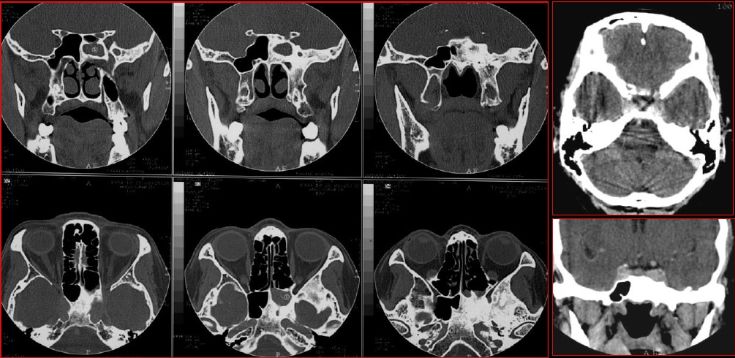

慢性鼻窦炎—黏膜改变

慢性鼻窦炎—黏膜囊肿

慢性鼻窦炎—积液

慢性多发鼻窦炎鼻息肉

慢性多发鼻窦炎—MRI